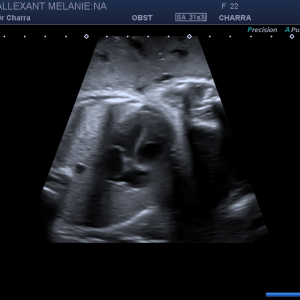

Suivi de votre grossesse avec réalisation des échographies recommandées, Prise en charge des IVG medicamenteuses (en lien avec la maternité de Beaune), infertilité, prise en charge des douleurs pelviennes (endométriose par exemple)

Suivi Echographique seul lorsque le suivi clinique est assuré par un autre professionnel de santé

Echographies gynécologiques, Monitorage de l'ovulation (parcours PMA)

Diplômée en Echographie foetale et Gynécologique

Diplômée en Médecine Foetale

Agrément National pour la réalisation des échographies du Premier Trimestre de grossesse

Membre du Collège d'Echographie Foetale Français (CFEF)